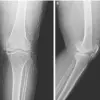

During an X-ray to assess her knee condition, doctors were stunned to discover hundreds of tiny gold threads embedded deep within her joints, a byproduct of a prior acupuncture treatment.

The X-ray revealed the threads clustered around her kneecaps, extending into her shin bone and upper thigh—a distribution that could interfere with future diagnostic imaging. ‘This is a textbook example of how alternative treatments can complicate medical care,’ said Dr.

Min-Young Park, a radiologist at Seoul National University Hospital, who reviewed the scans. ‘These threads were so numerous and diffuse that they obscured critical anatomical details, making it harder to assess the full extent of her osteoarthritis.’